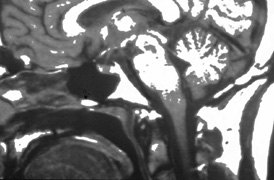

Optic nerve hypoplasia, unless subtle, usually is diagnosed on fundus examination. Although most cases are idiopathic, maternal gestational diabetes and use of phenytoin are well-known risk factors; more recent epidemiologic studies have also suggested that young maternal age, first parity, smoking, and use of fertility and antidepressant drugs may also play a role.27 If bilateral, this condition may be associated with congenital nystagmus. De Morsier's syndrome (septo-optic dysplasia) refers to the constellation of bilateral optic nerve hypoplasia, absence of the septum pellucidum (Fig. 5), thinning or absence of the corpus callosum, dysplasia of the anterior third ventricle, and pituitary dysfunction (see Chapter 5, Fig. 9). Brodsky and Glasier28 broadened the spectrum of this condition. In a study of 40 children, some optic nerve anomalies were isolated, but in other children, midline craniofacial defects, hemispheric gray matter dystrophic anomalies, and posterior pituitary ectopia were noted. Of 21 cases of optic nerve hypoplasia described by Zeki et al,29 there were midline central nervous system defects in six and endocrine deficiencies in nine. In the series of 35 patients with bilateral optic nerve hypoplasia described by Siatkowski et alet al30 neuroradiographic abnormalities were seen in 46% and endocrinopathies in 27%. Growth hormone deficiency was the most common endocrine abnormality. The visual spectrum ranged from 20/20 in one case to no light perception in 34% of patients; 80% were legally blind (20/200 or less in both eyes). Absence of the septum pellucidum and corpus callosum, with panhypopituitarism, occurred in only 11.5% of all patients with bilateral optic nerve hypoplasia. Recently, a sporadic mutation in the HESX1 gene has been reported to cause optic nerve hypoplasia with pituitary insufficiency.31

Fig. 5. Magnetic resonance image of patient with bilateral optic nerve hypoplasia demonstrating absence of septum pellucidum with single midline ventricle.